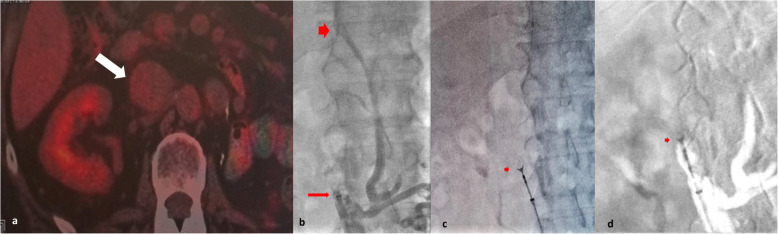

Fig. 1.

a 18F-FDG PET/CT image indicating the low 18F-FDG uptake of the IVC thrombosis (arrow). b Angiographic image indicating the sheath of the kit (arrow) within the proximal segment of the thrombosed IVC at the level of L1-L2 vertebra. Note that the thrombosis extends up to the level of T12vertebra (arrowhead). c Fluoroscopic and (d) roadmap images demonstrating the opened forceps (arrow) at the mid segment of the lesion, just before sampling